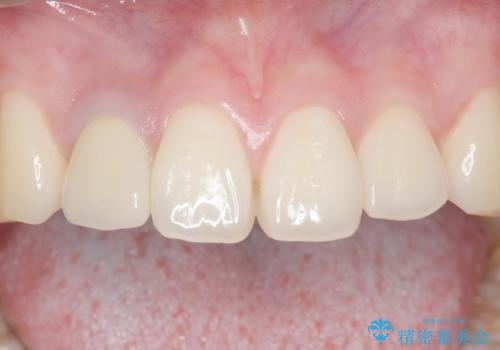

土台を白いファイバーコアにやりかえたのち、土台の色を透過させないジルコニアフレームを用いたセラミッククラウンによる治療を行いました。

自然な仕上がりにご満足頂けました。

治療終了時には「修正や仮付けをしてもらえて納得のいく治療を受けられました。この病院にして良かったです!」とおっしゃって下さいました。

クラウンの種類:オールセラミッククラウン スペシャル